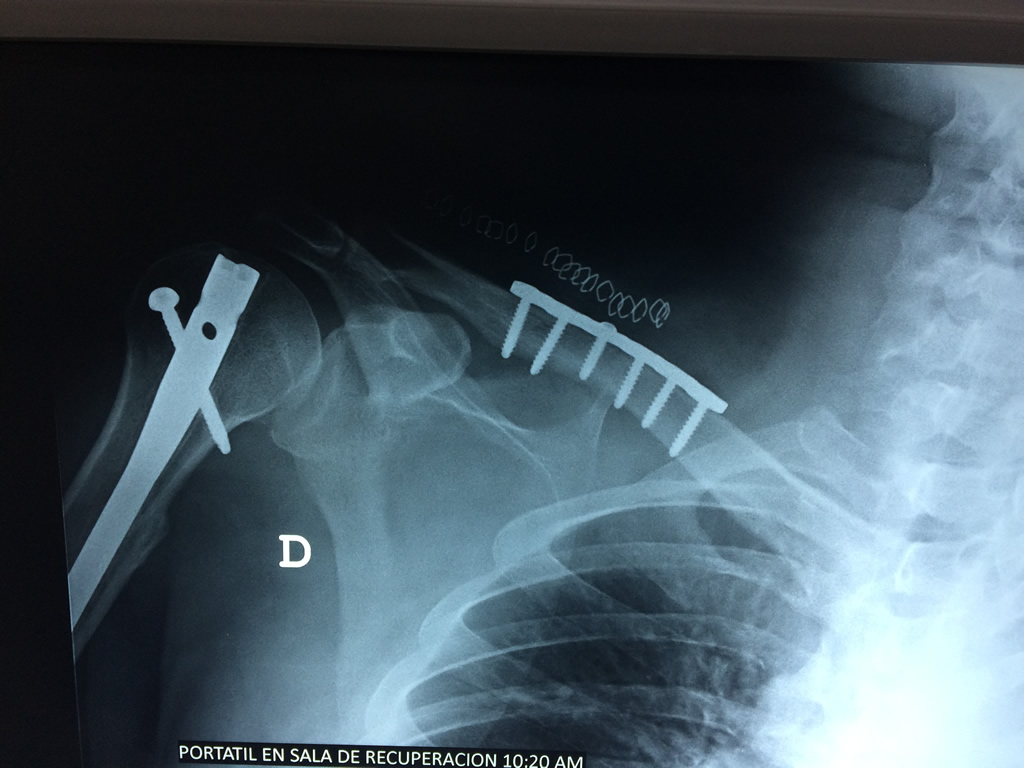

Cirugías de Codos - Clavícula

La clavícula es un hueso largo, con forma de "S" itálica, situado en la parte anterosuperior del tórax. Junto con la escápula forman la cintura escapular. Se puede palpar por toda su longitud y se extiende del esternón al acromion de la escápula, siguiendo una dirección oblicua lateral y posterior.

Se considera el único medio de unión entre el miembro superior y el tórax. A pesar de su aspecto, similar al de un hueso largo, posee una estructura semejante a la de un hueso plano, ya que carece de epífisis y de diáfisis, lo que la harían entrar dentro de la clasificación de hueso largo. Carece de un canal medular propiamente dicho.